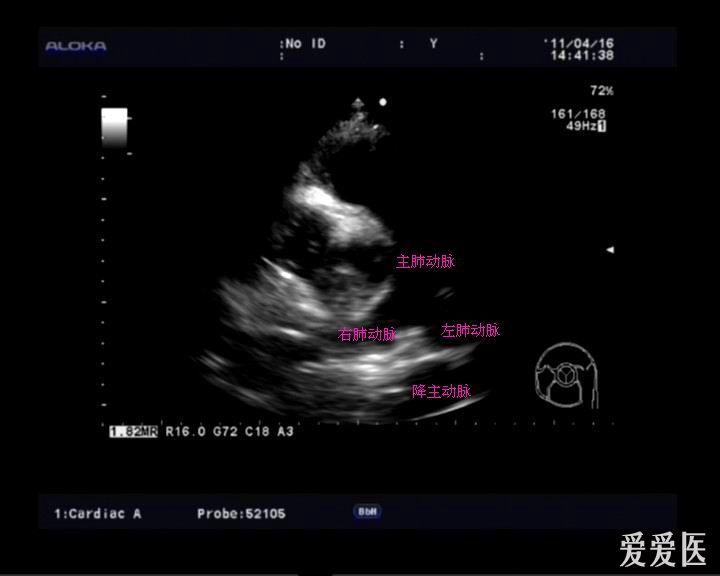

三腔心切面

三腔心切面,

图1.28 三腔心视图.

心不够饱满,可以上翘下压适当调整,或者,继续逆时针转,打出三腔心之后